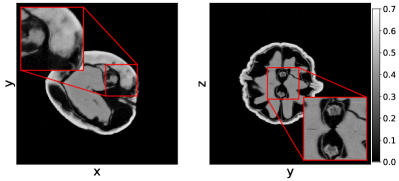

In Figure 7 we show the average and standard deviation of the TSE and the SSIM for the considered cases. We observe that U-net and MSD achieve the most accurate results and that NN-FDK and SIRT+ closely follow. The FDK algorithm is lowest in all categories. Between NN-FDK and SIRT+ we see that NN-FDK performs best for the noisy reconstruction problems and SIRT+ achieves better results for the reconstruction problems without noise. We visualize the noise for the lowest and highest in Figure 8 by showing a line profile through the center of the slice. Here we see that for the noisiest problems the amplitude of the noise can be as high as the maximum value of the phantom. In Figure 9 we show 2D slices of reconstructions of the test phantoms for the three types of reconstruction problems. In all cases we still observe reconstruction artifacts, but comparing these to the baseline FDK reconstructions, the majority is removed or suppressed.

Comparing the results to the simulated data experiments we see that SIRT+ performs worse on the experimental data, even with the additional regularization of early stopping. This is most likely due to the high-dose datasets still containing noise, whereas this is completely absent in the simulated data experiments. These differences are illustrated in Figure 10 where 2D slices of the reconstructions for the high-dose reconstruction problem with projection angles are shown.